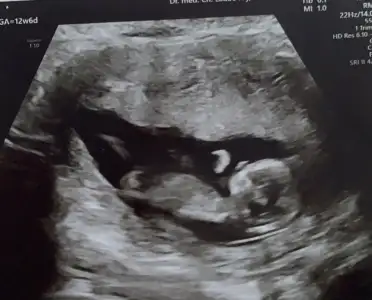

Simdi 17 haftaligiz. Bu resimlerdede 12 haftaydi

Attım tekrar bundan baslada yok 12+3